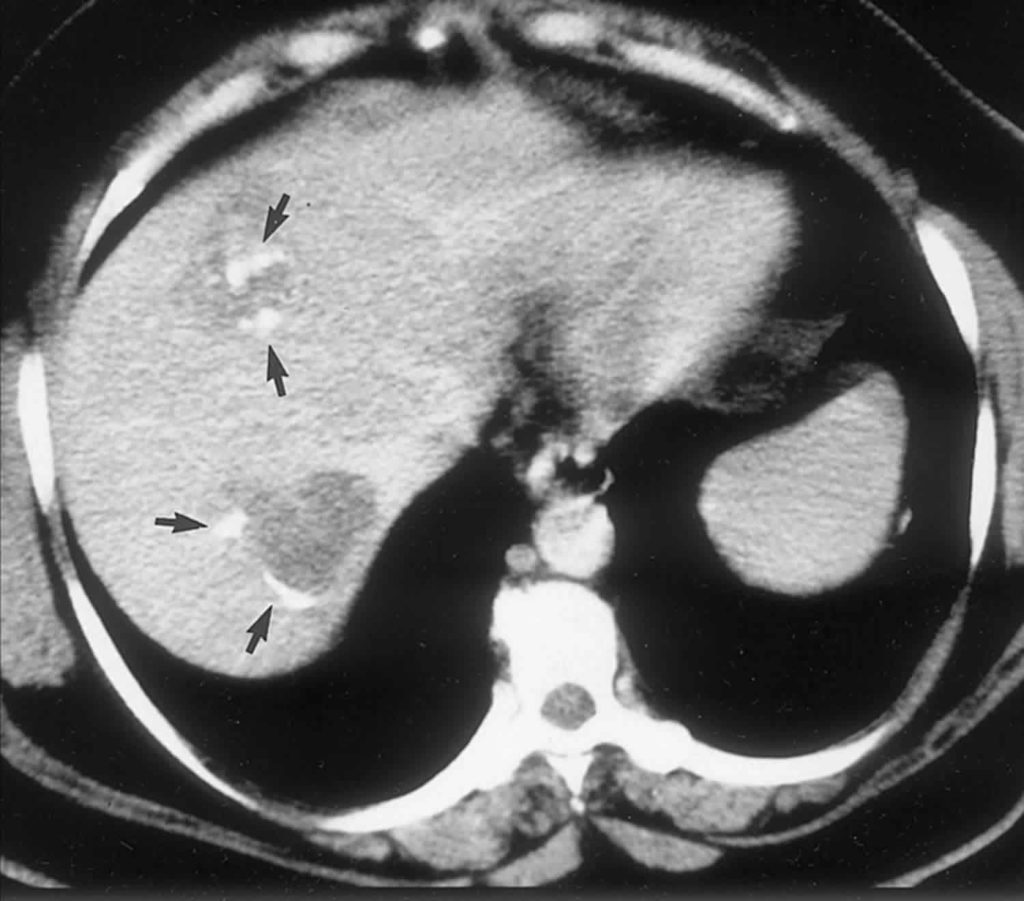

CT scan of the liver cyst. Download Scientific Diagram Liver Cyst Reddit If the cyst is large enough, it could have been a factor in your reflux issues. We also cover diagnosis and treatment and what cystic. If that were the case, it would have gradually gotten worse over time. In this article, we explore the causes, symptoms, and complications of liver cysts and when to see a doctor. I have tons. Liver Cyst Reddit.